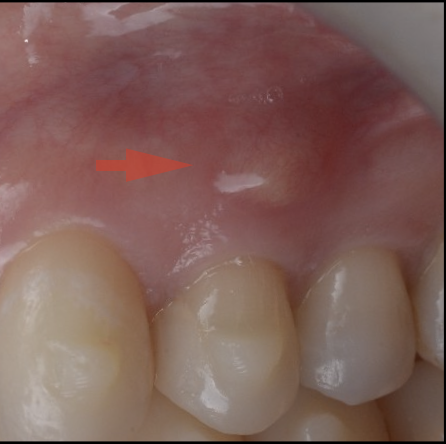

上唇の腫脹を認め、CT検査にて根尖部に嚢胞様透過像を認めた。左上の前歯が不自然に大きく噛み合わせが強くなっていたことがフレアアップの一因と考える。精密根管治療を行い、感染経路を遮断したのち歯根端切除術にて嚢胞を摘出した。

治療前

治療中

治療中